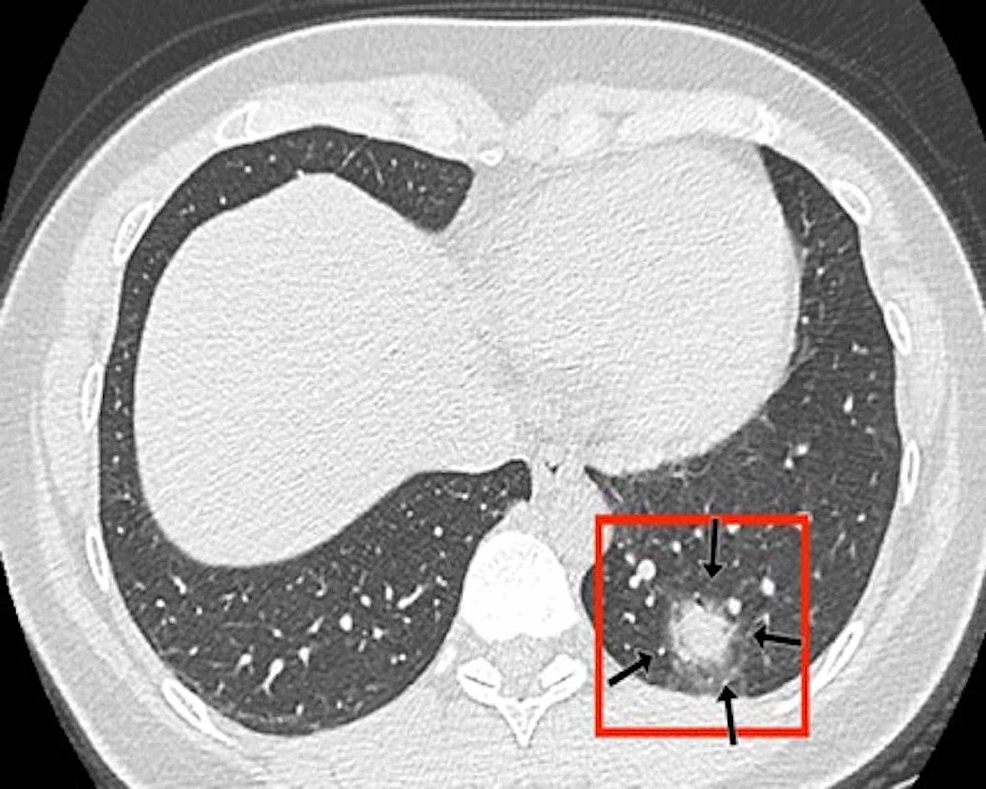

Two board-certified radiologists (E.P. and U.M., with 25 and five years of experience, respectively) reviewed the chest CT images on a picture archiving and communication system (PACS, Carestream Health, Inc, Rochester, NY). Chest CT images were evaluated with both mediastinal (width: 350 HU, level: 40 HU) and lung (width: 1500 HU, level: -500 HU) window level settings. The two radiologists identified pulmonary lesions based on their density, shape, and margin. The locations of the lung lesions were recorded as lobar, axial, anterior, and posterior. Axial locations were categorized as central (inner two-thirds of the lung) or peripheral (outer one-third of the lung). Each lung was divided by an axial line into anterior and posterior halves (Figures 2, 7). The densities of the patchy-confluent lesions were classified as pure GGO, pure consolidation, or mixed. Nodular lesion densities were classified as pure GGO, solid, or partly solid. Margins were classified as well-defined or ill-defined. As most of the lesions were patchy, confluent, and ill-defined margins, lesion sizes were not assessed. Instead, a visual severity score, which was slightly modified from Pan et al., ranging from 0 to 4 for each individual lobes was calculated. Each of the five lung lobes was visually scored on a scale of 0 to 4 as follows: 0: no involvement; 1: less than 25% involvement; 2: 25-50% involvement; 3: 50-75% involvement; and 4: 75-100% involvement.

In the CT images, GGO plus consolidation was observed bilaterally in all 18 (100%) patients. No pure GGO or pure consolidation was encountered in our cohort. The predominant shape was amorphous (72%). Lesions showed no specific lobar predilection, but most lesions were localized posteriorly and peripherally.

The distinctive CT features in our cohort are summarized in Table 3, including GGO and consolidative patchy mostly amorphous (72%) lesions, bilateral posterior and peripheral multi-lobar lung involvement, pleural effusions, subpleural fibrotic lines, subpleural sparing, vascular engorgement, occasional crazy paving, occasional mediastinal lymphadenopathy, pleural thickening, lack of cavitation, and absence of reverse halo (atoll) signs.

Subpleural sparing, which was observed in this patient cohort, has never been reported before, whereas mediastinal lymphadenopathy has been reported occasionally in the literature in English [11]. Focal vascular engorgement, septal thickening, and a subpleural fibrotic line were seen frequently in our cohort, with frequencies of 83%, 72%, and 61%, respectively.

Patients’ CT features are presented in detail in Figures 3, 4, 5, 6, 7, 8. A majority of cases (56%) had moderate severity scores. There was no correlation between the severity score and mortality, p=0.790 (Table 4).